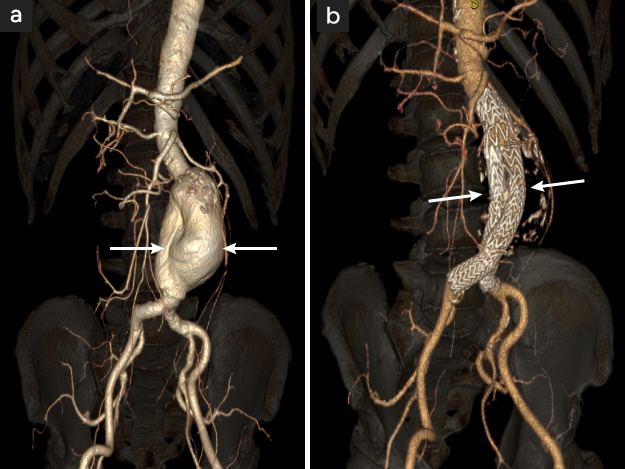

ステントグラフト留置術(EVAR:Endo-Vascular Aneurysm Repair)

金属性の格子状の筒を人工血管布で包んだステントグラフト(既成人工血管)をカテーテルで動脈瘤内に誘導して内腔に留置する方法です。低侵襲ですので高齢者や全身状態の不良な患者さんに適しています〈図3 a,b〉。

図3

図3. 腹部大動脈瘤に対するステントグラフト留置術

88才/男性

77mmの巨大瘤

• 術前大動脈造影腹部大動脈瘤が描出される(矢印)

• 腹部大動脈瘤に留置されたステントグラフト(白い網状の金属とそれを覆う 人工血管布)が描出されるステントグラフトExcluder(手術時間1時間56分)